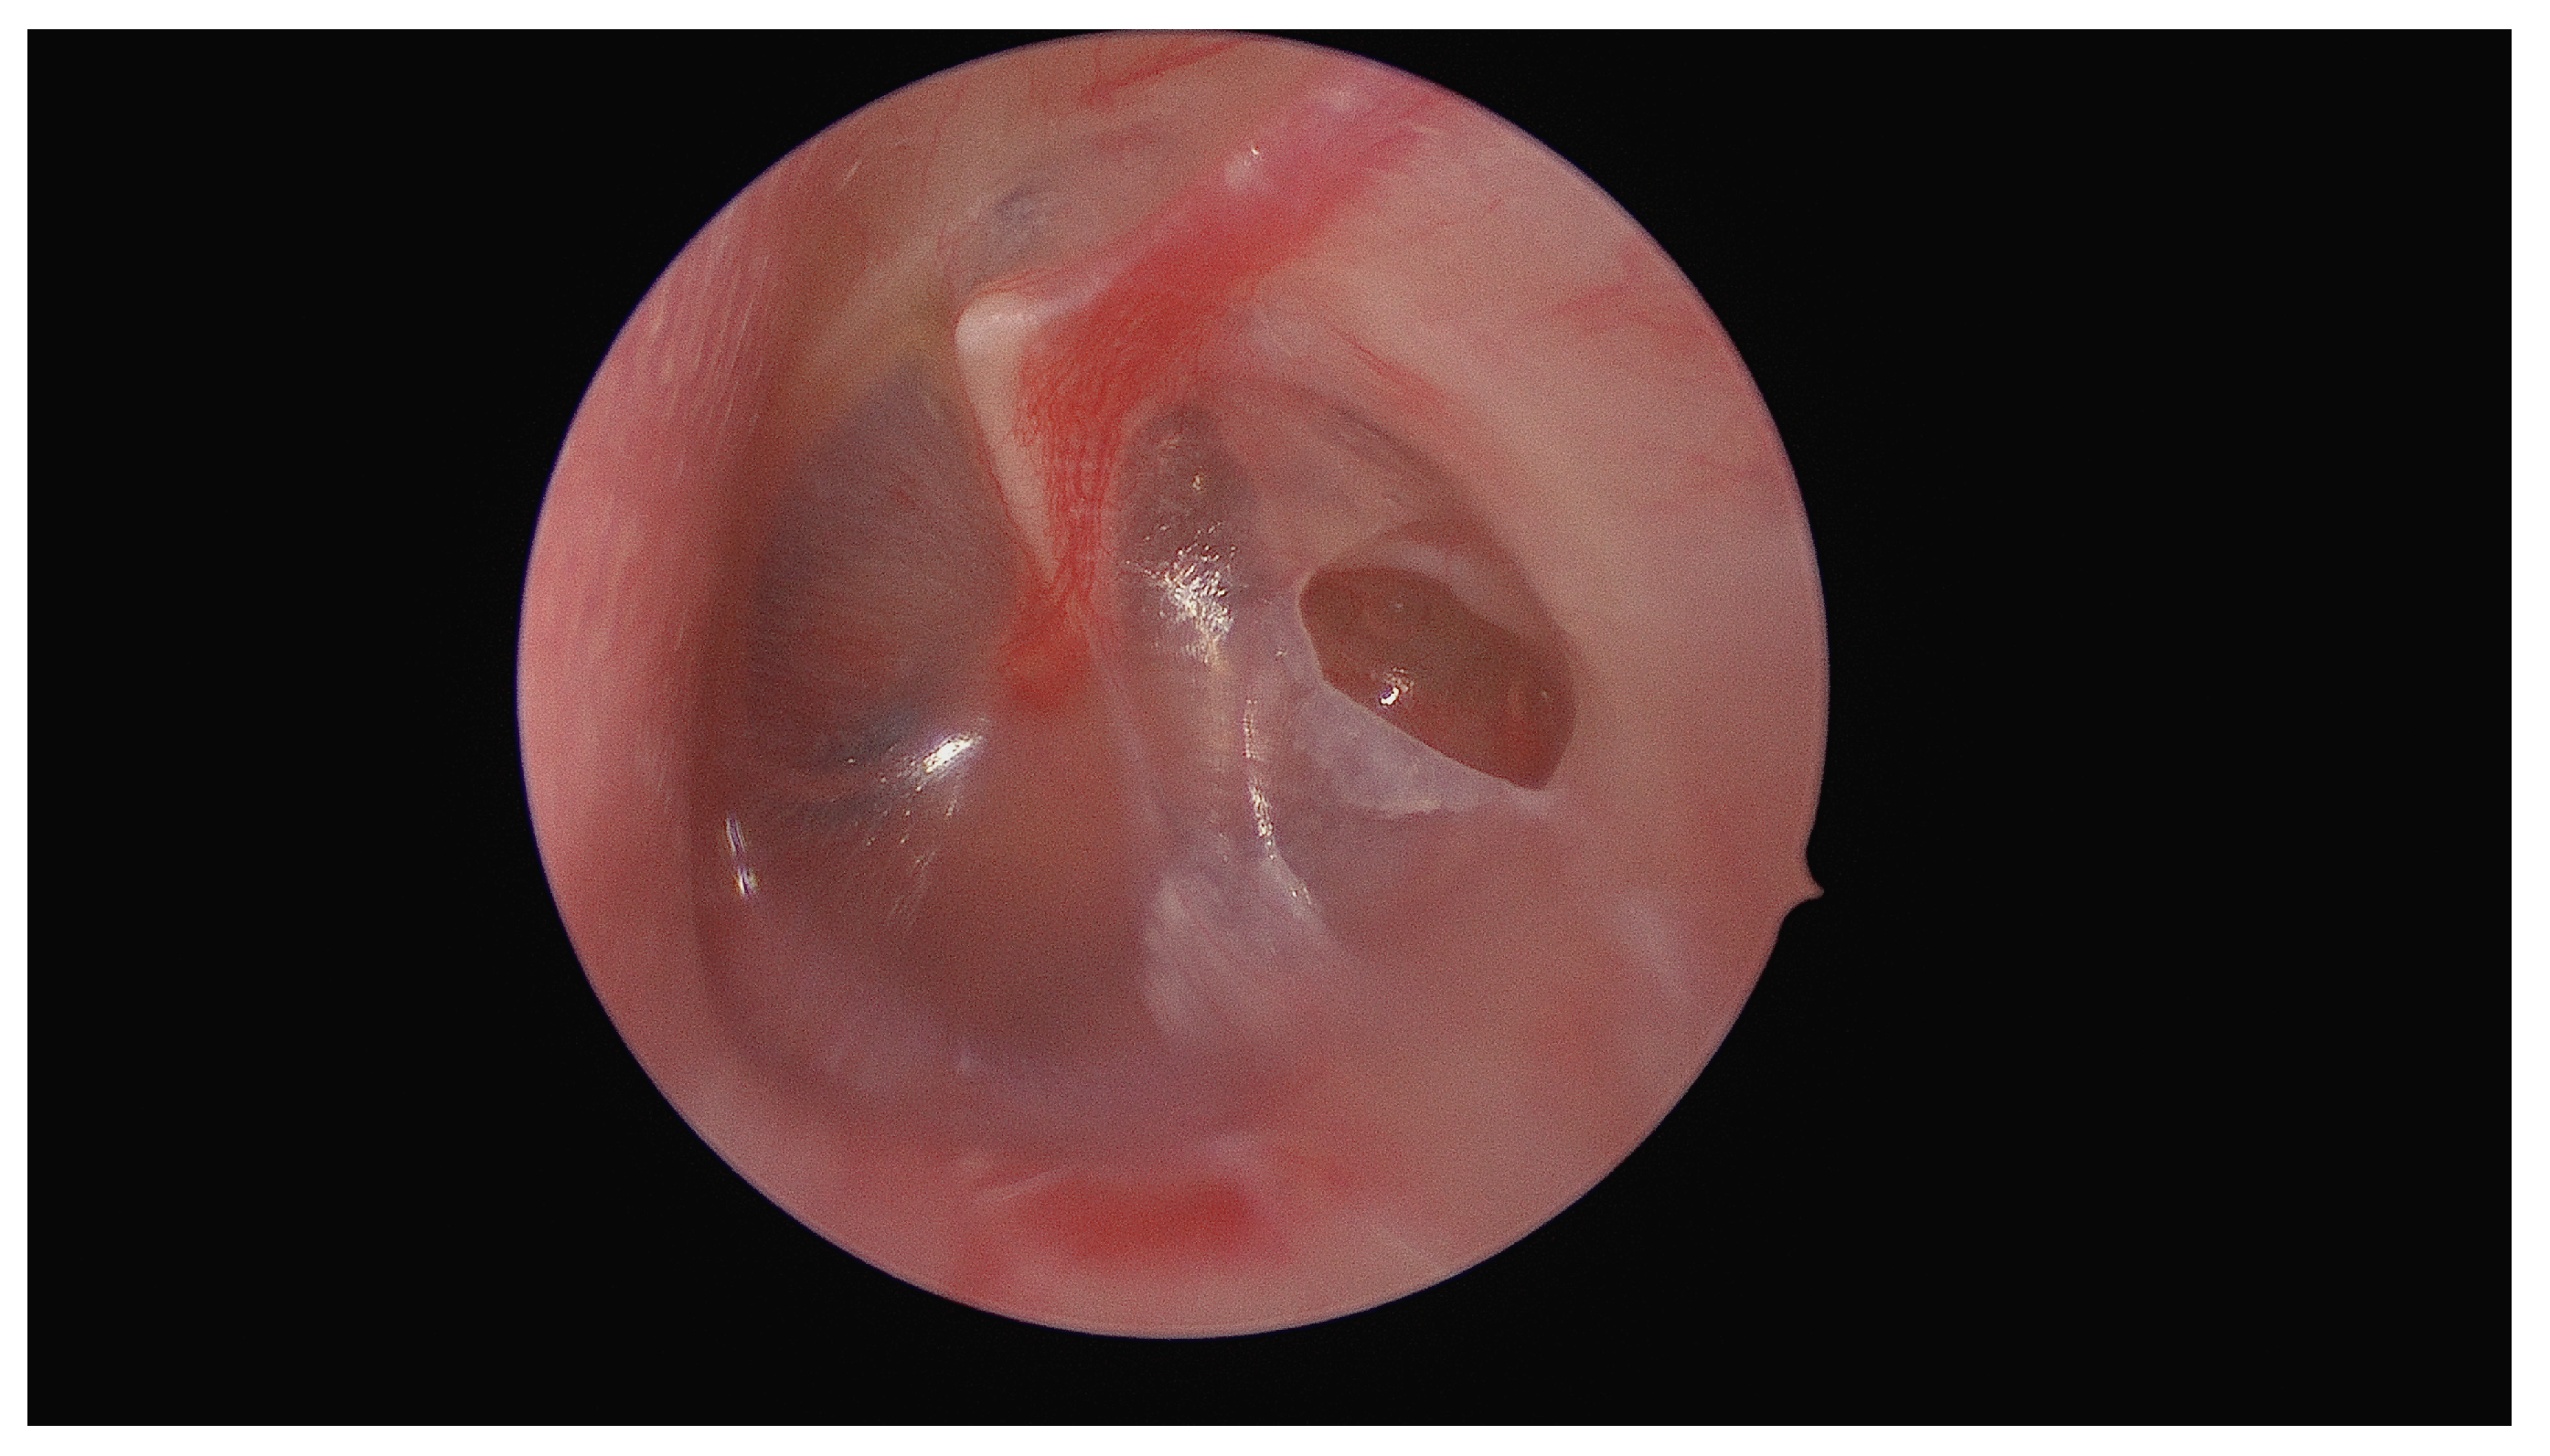

Unusual Foreign Body in the Middle Ear: Surgical Removal of a Live Ant Entering the Tympanic Cavity Through an Ear Drum Perforation

Kiss, P.; Pock, J.; Habenbacher, M.; Maitz, E.; Lang, A.; Walla, K.; Andrianakis, A. Unusual Foreign Body in the Middle Ear: Surgical Removal of a Live Ant Entering the Tympanic Cavity Through an Ear Drum Perforation. Diagnostics 2024, 14, 2530. https://doi.org/10.3390/diagnostics14222530